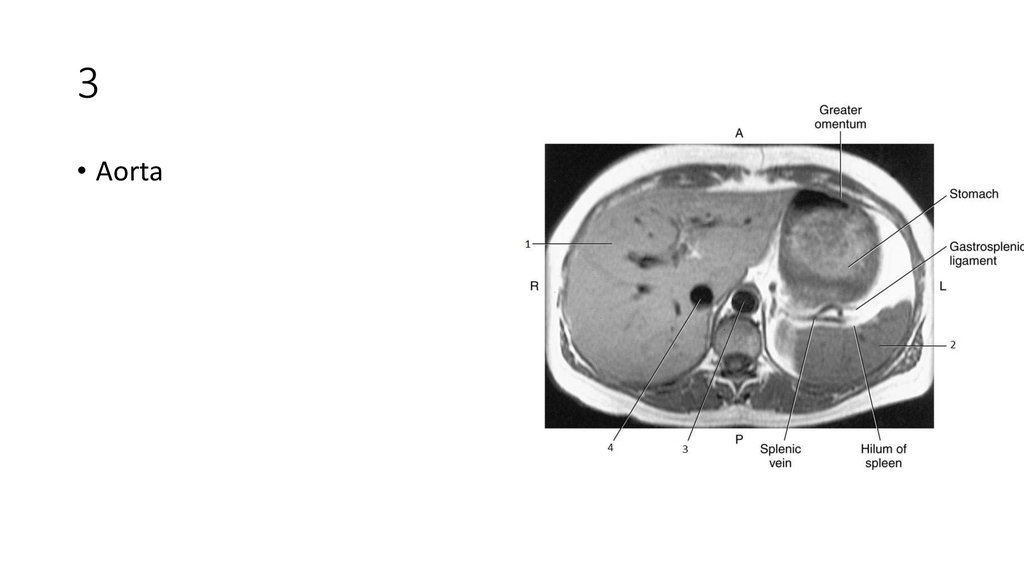

16. 1

17. 1

• Falciform Ligament

18. 2

19. 2

• Left lobe of Liver

20. 3

21. 3

• Spleen

22. 4

23. 4

• Aorta

24. 5

25. 5

• Caudate Lobe of Liver

26. 6

27. 6

• Right Lobe of Liver

28. 7

29. 7

• Inferior Vena Cava (IVC)

30. 8

31. 8

• Portal Vein